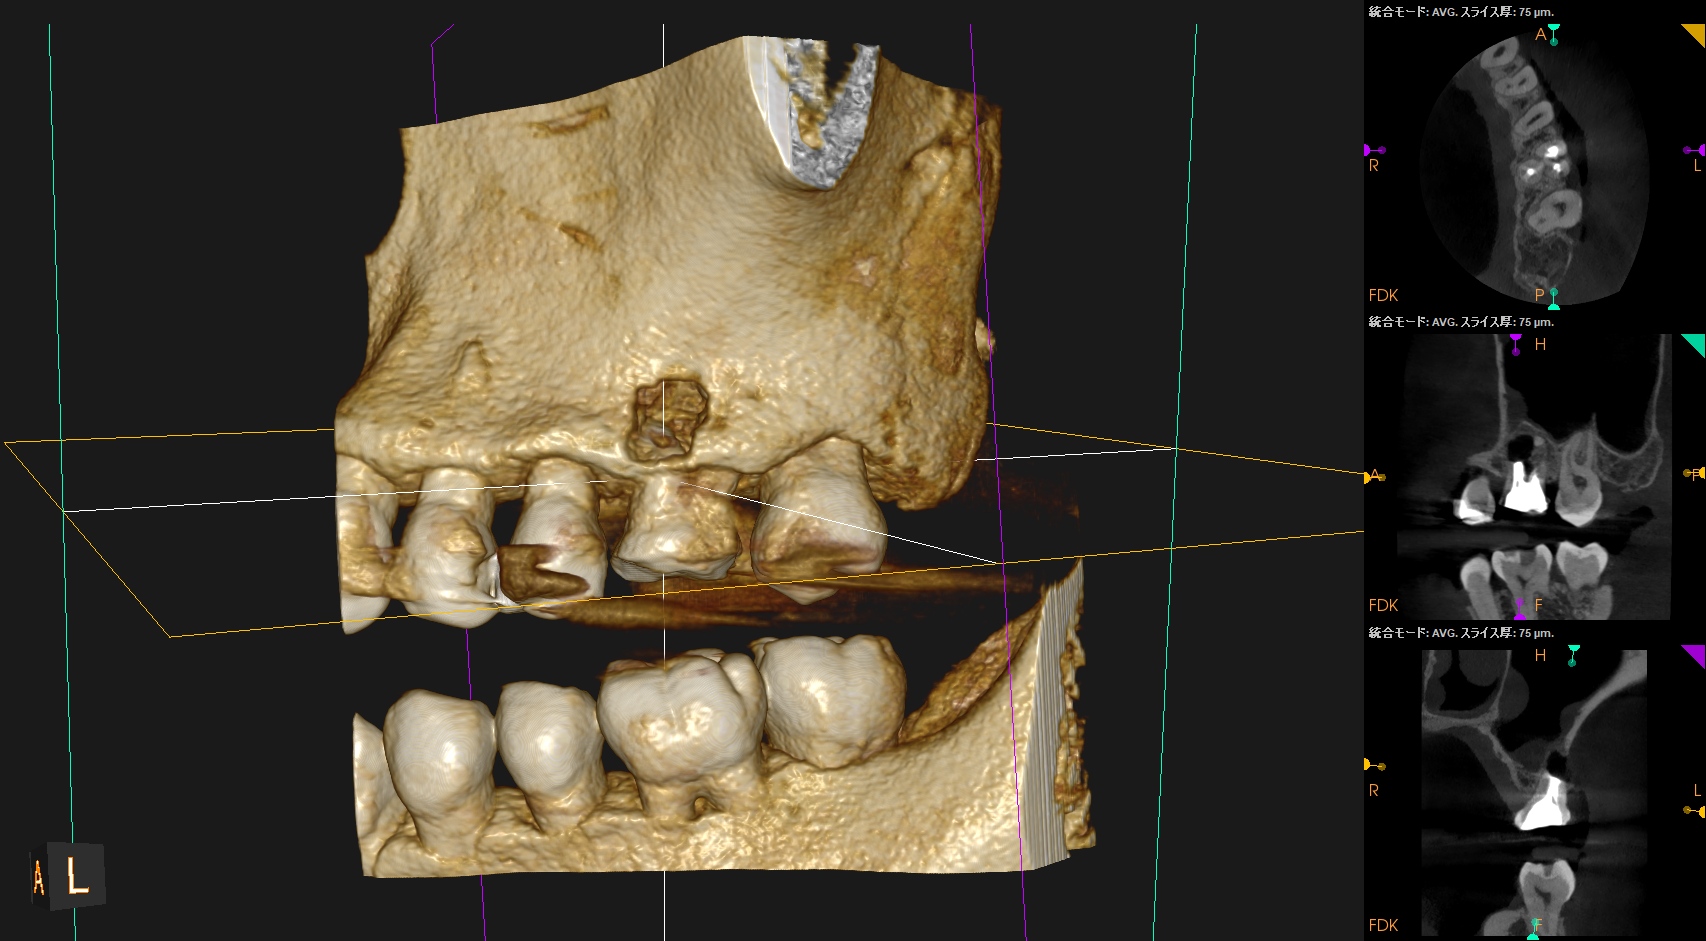

#14 Core build up, Perforation Repair(2025.4.15)

MBは穿孔部ごとBC sealer, BC Puttyで充填した。

この後Apicoectomyになるから問題はない。

同日、MBのApicoectomyを行った。

MBのApexを見つけることなく、CEJから5.5mmの位置で頬舌的幅径5mmの長さで切断し、Apex周囲の骨を削除しApexを取り除いた。

その後、メチレンブルーで染色し逆根管形成に移行する。

その際はBC sealerのみであるのでGutta Percha Pointの残渣に悩まされることがない。かなり時短できるだろう。非常にEasyなApicoectomyだ。

これが私が穿孔封鎖とApicoectomyを同日に行なった理由である。

術後にPA, CBCTを撮影した。

問題はないだろう。

縫合して終了した。